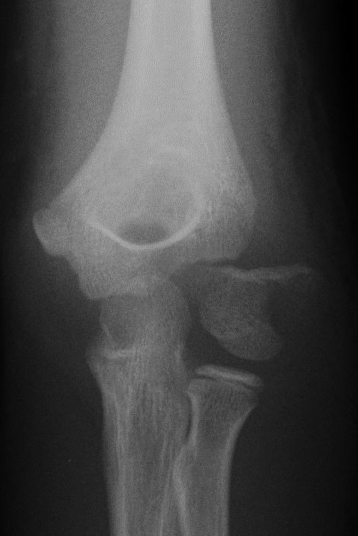

上腕骨外側顆骨折のX線像(典型例)

Jakob分類Ⅲ型

出典

img

1: 著者提供